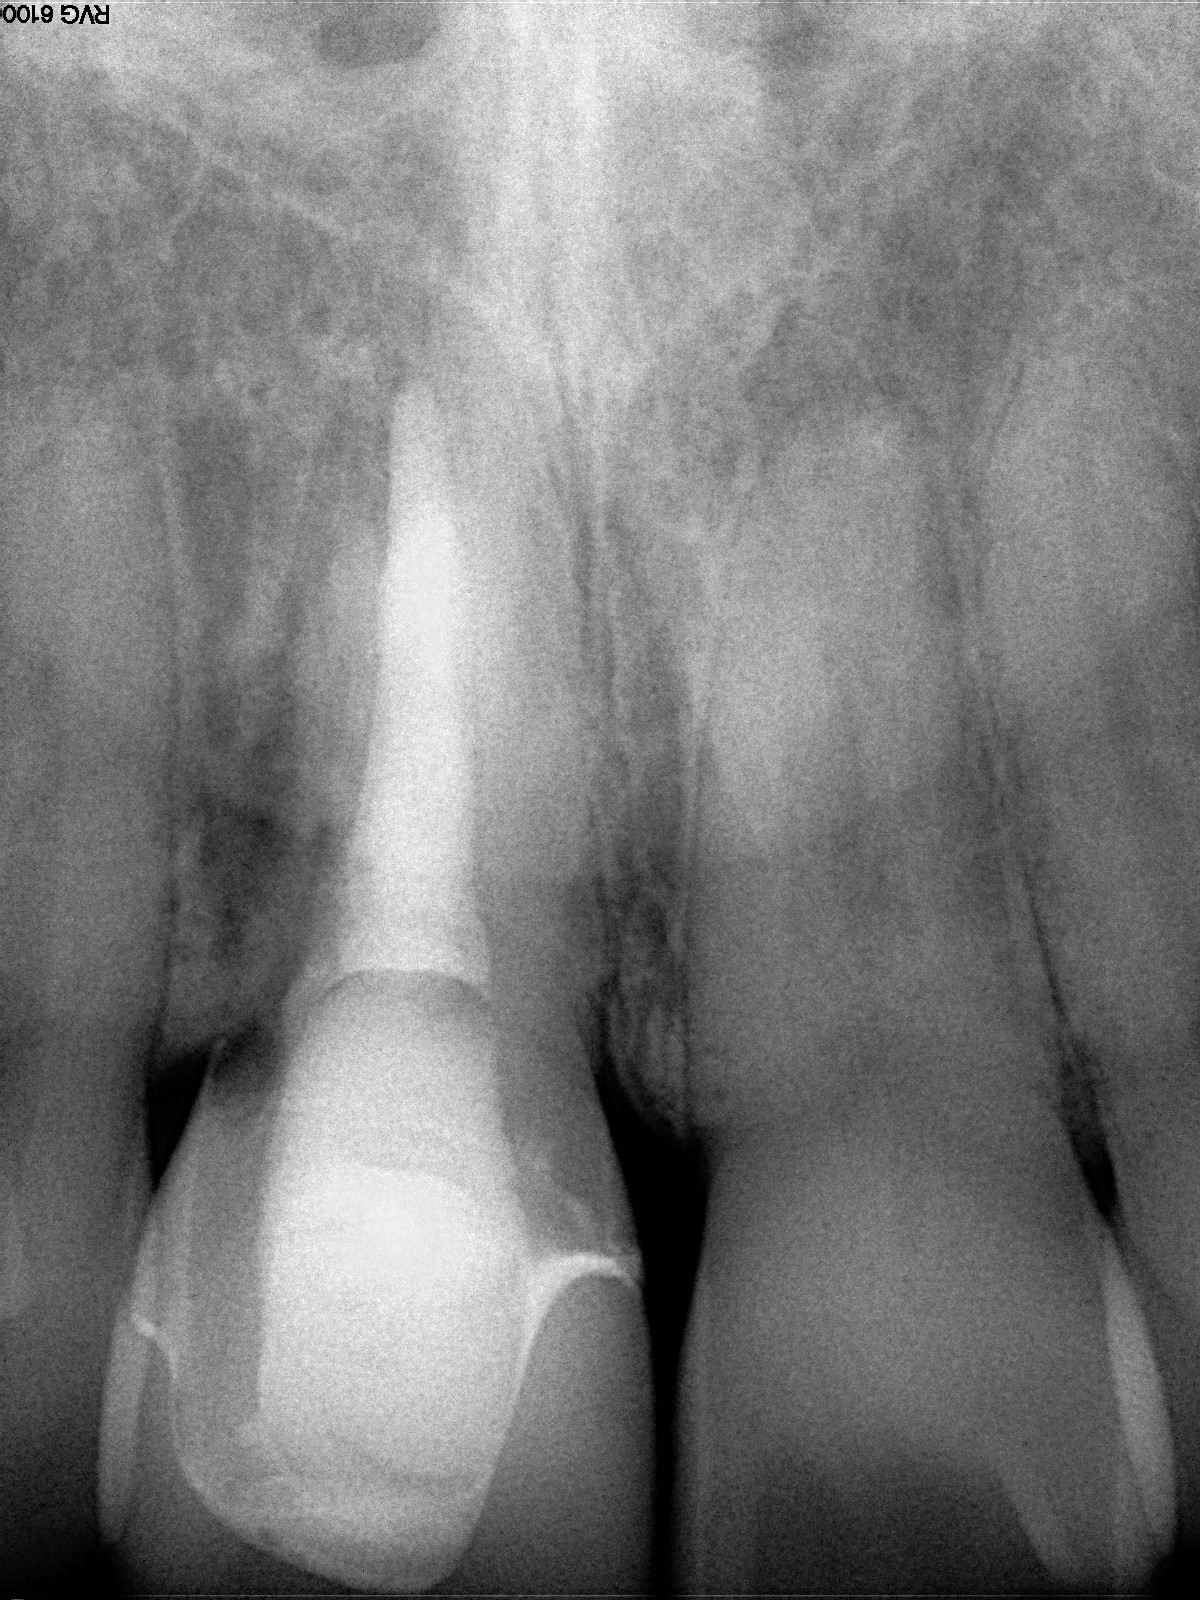

Plugging into digital workflows provides opportunities to integrate CAD/CAM technologies at every step of the treatment process for dental implants. In another example, a patient presented with a failing tooth No. 8 (Figure 6 and Figure 7). After discussing treatment options, the patient chose to forgo any treatment to address tooth and soft-tissue asymmetries and wanted to proceed with a dental implant-supported restoration without additional treatment. After integrated 3-dimensional planning, the tooth was extracted, and then an implant and the final custom CAD/CAM abutment (titanium base with zirconia supra-structure) were placed with a provisional restoration in the same visit (Figure 8 and Figure 9). Soft-tissue grafting was also done at the same visit to address the deficient buccal tissue height on No. 8 (Figure 10). At 3 months, the patient presented for the final restoration, with excellent healing around the implant (Figure 11) and soft-tissue healing guided by the custom abutment (Figure 12).

Fig 6. Clinical presentation of patient with a failing tooth No. 8.

Figure 6

Fig 7. Preoperative radiograph showing previous endodontic therapy on tooth No. 8.

Figure 7